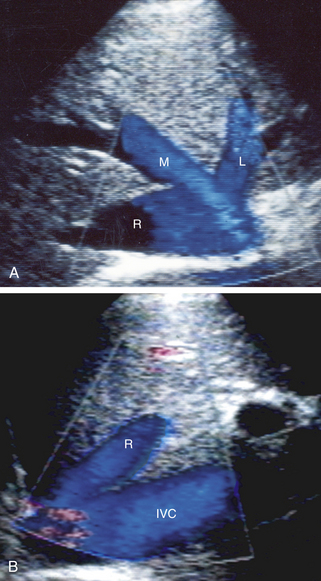

Печеночные вены лучше всего визуализируются с помощью ультразвука с использованием поперечного подмечевидного доступа, который дает изображение трех основных печеночных стволов, сходящихся на НПВ, как это видно на рис. 26-12 , А. Однако с этой точки зрения кровоток часто Правую печеночную вену при цветном допплеровском исследовании невозможно визуализировать, поскольку ось этой вены перпендикулярна лучу ультразвука. Правая печеночная вена лучше просматривается при продольном сканировании и межреберном положении датчика ( рис. 26-12 , Б ).

РИСУНОК 26-12. УЗИ печеночных вен. А. Поперечный вид трех основных стволов печеночных вен в момент их входа в нижнюю полую вену. L, левая печеночная вена; М, средняя печеночная вена; R, правая печеночная вена. B: фронтальная проекция: правая печеночная вена (R) в месте ее соединения с нижней полой веной (НПВ).

Импульсные допплеровские сигналы, полученные из печеночных вен, отличаются от сигналов воротной вены. Печеночные вены имеют пульсирующий поток W- образной формы. Эта картина демонстрирует поток крови, который преимущественно направлен от печени к сердцу (гепатофугальный). Пульсация связана с сокращением предсердий и изменением направления тока крови обратно в печень ( рис. 26-13 ).